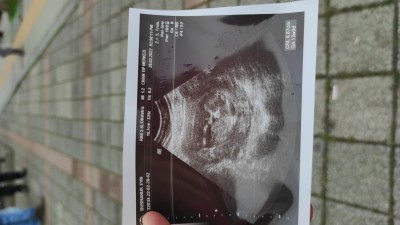

Kızlar merhaba bugün doktora gittim 13+1 1 hafta sonra gel dedi cinsiyet için. Çok heyecanlıyım meraktan ölüyorum:)) keseye göre cinsiyet diye bişey gördüm az önce internette,

imageböyle birşey varmı yorumlarınızı alabilir miyim bende ilk kez duydum :)

Gebelik haftası 13

Fasulye gibiyse erkek diye okudum int. Ve benmkide fasulye gibiydi erkek

Benimki daha yuvarlak sanki ama bı önceki ultrason resminde fasulye gibiydi :)